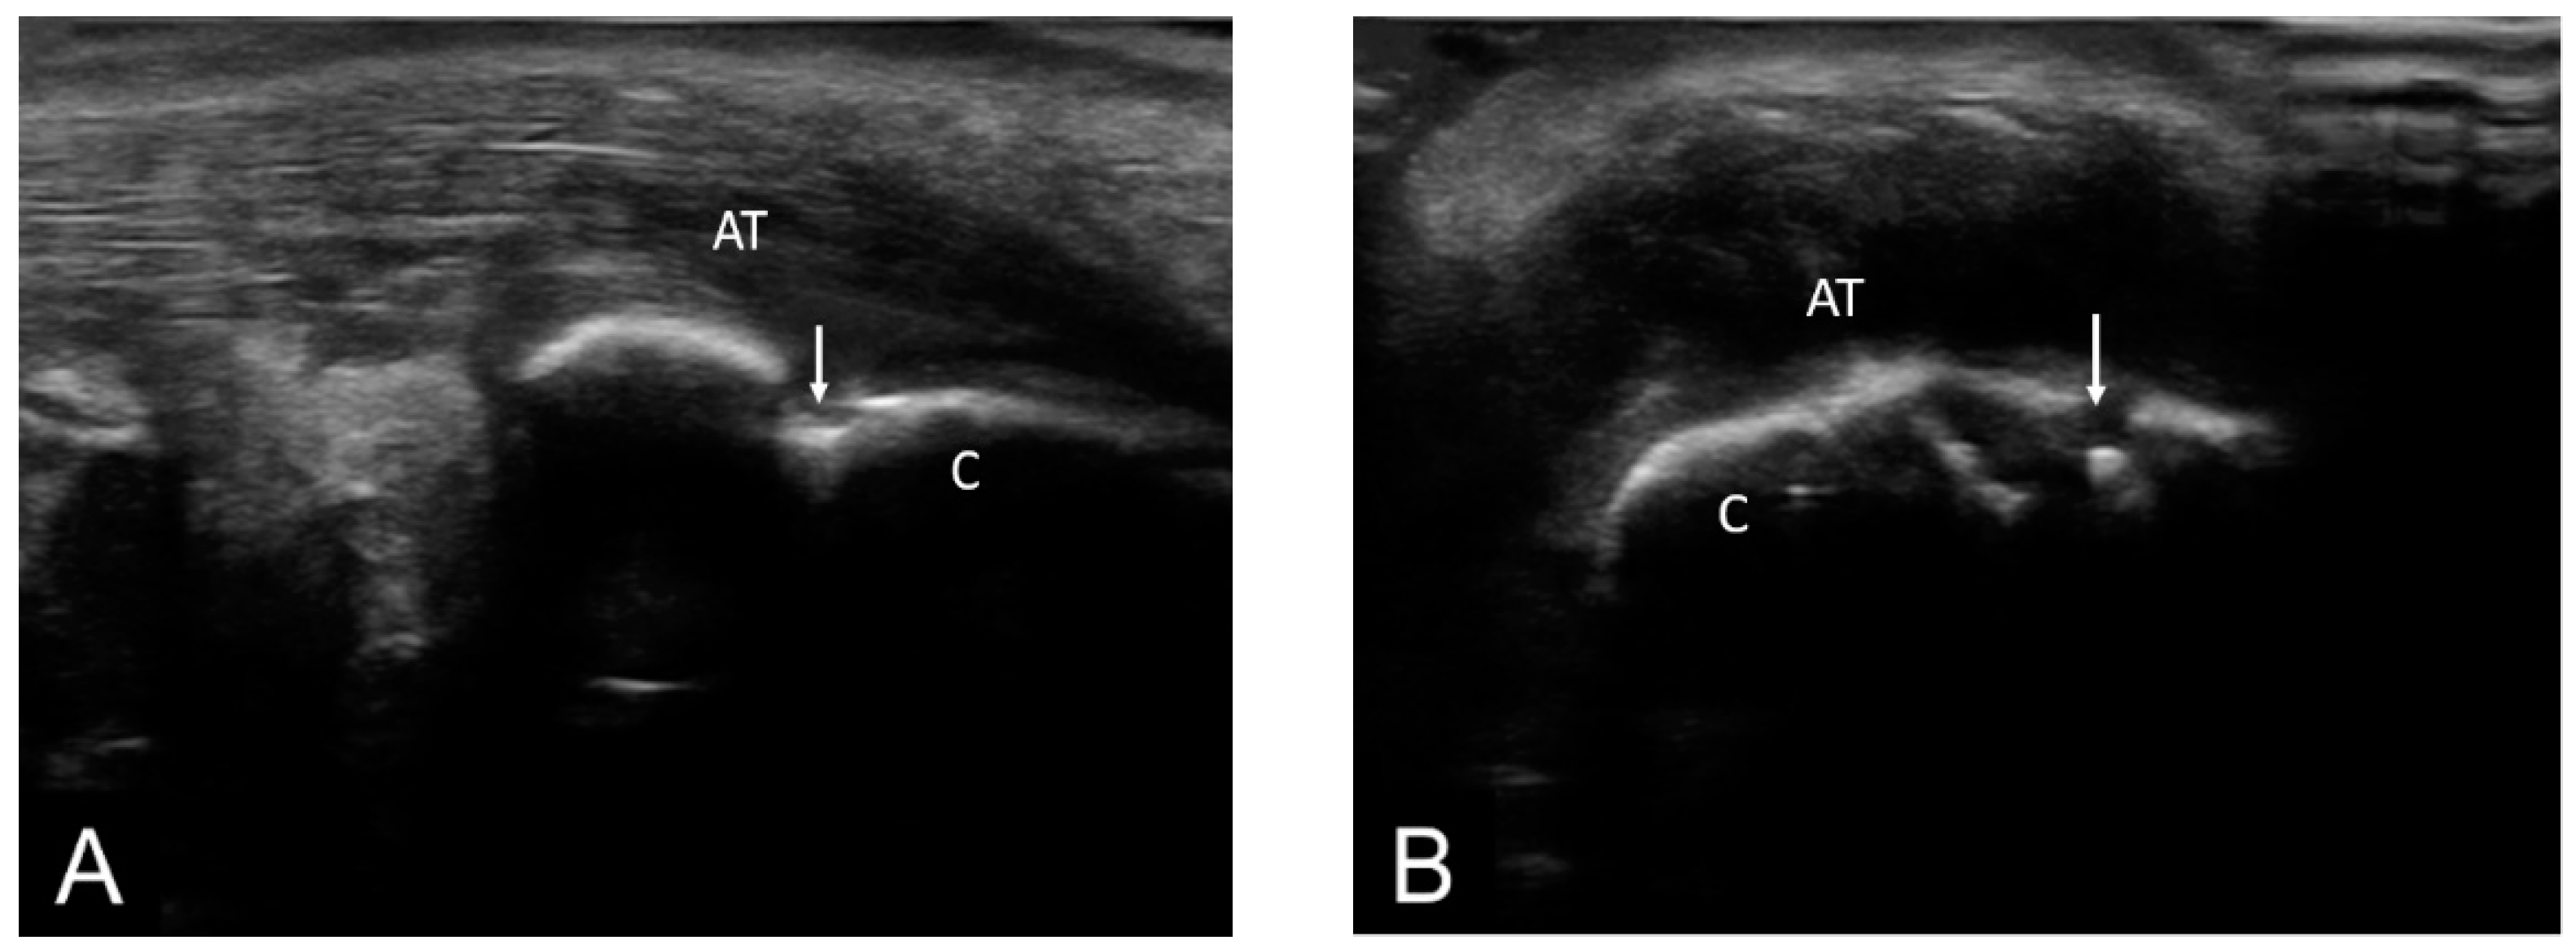

Figure 3. AT—Achilles tendon; C—calcaneus; ↓—calcaneus erosion; pathology—longitudinal (A) and transverse scan (B) in grey-scale of the Achilles tendon showing erosions in two perpendicular planes.